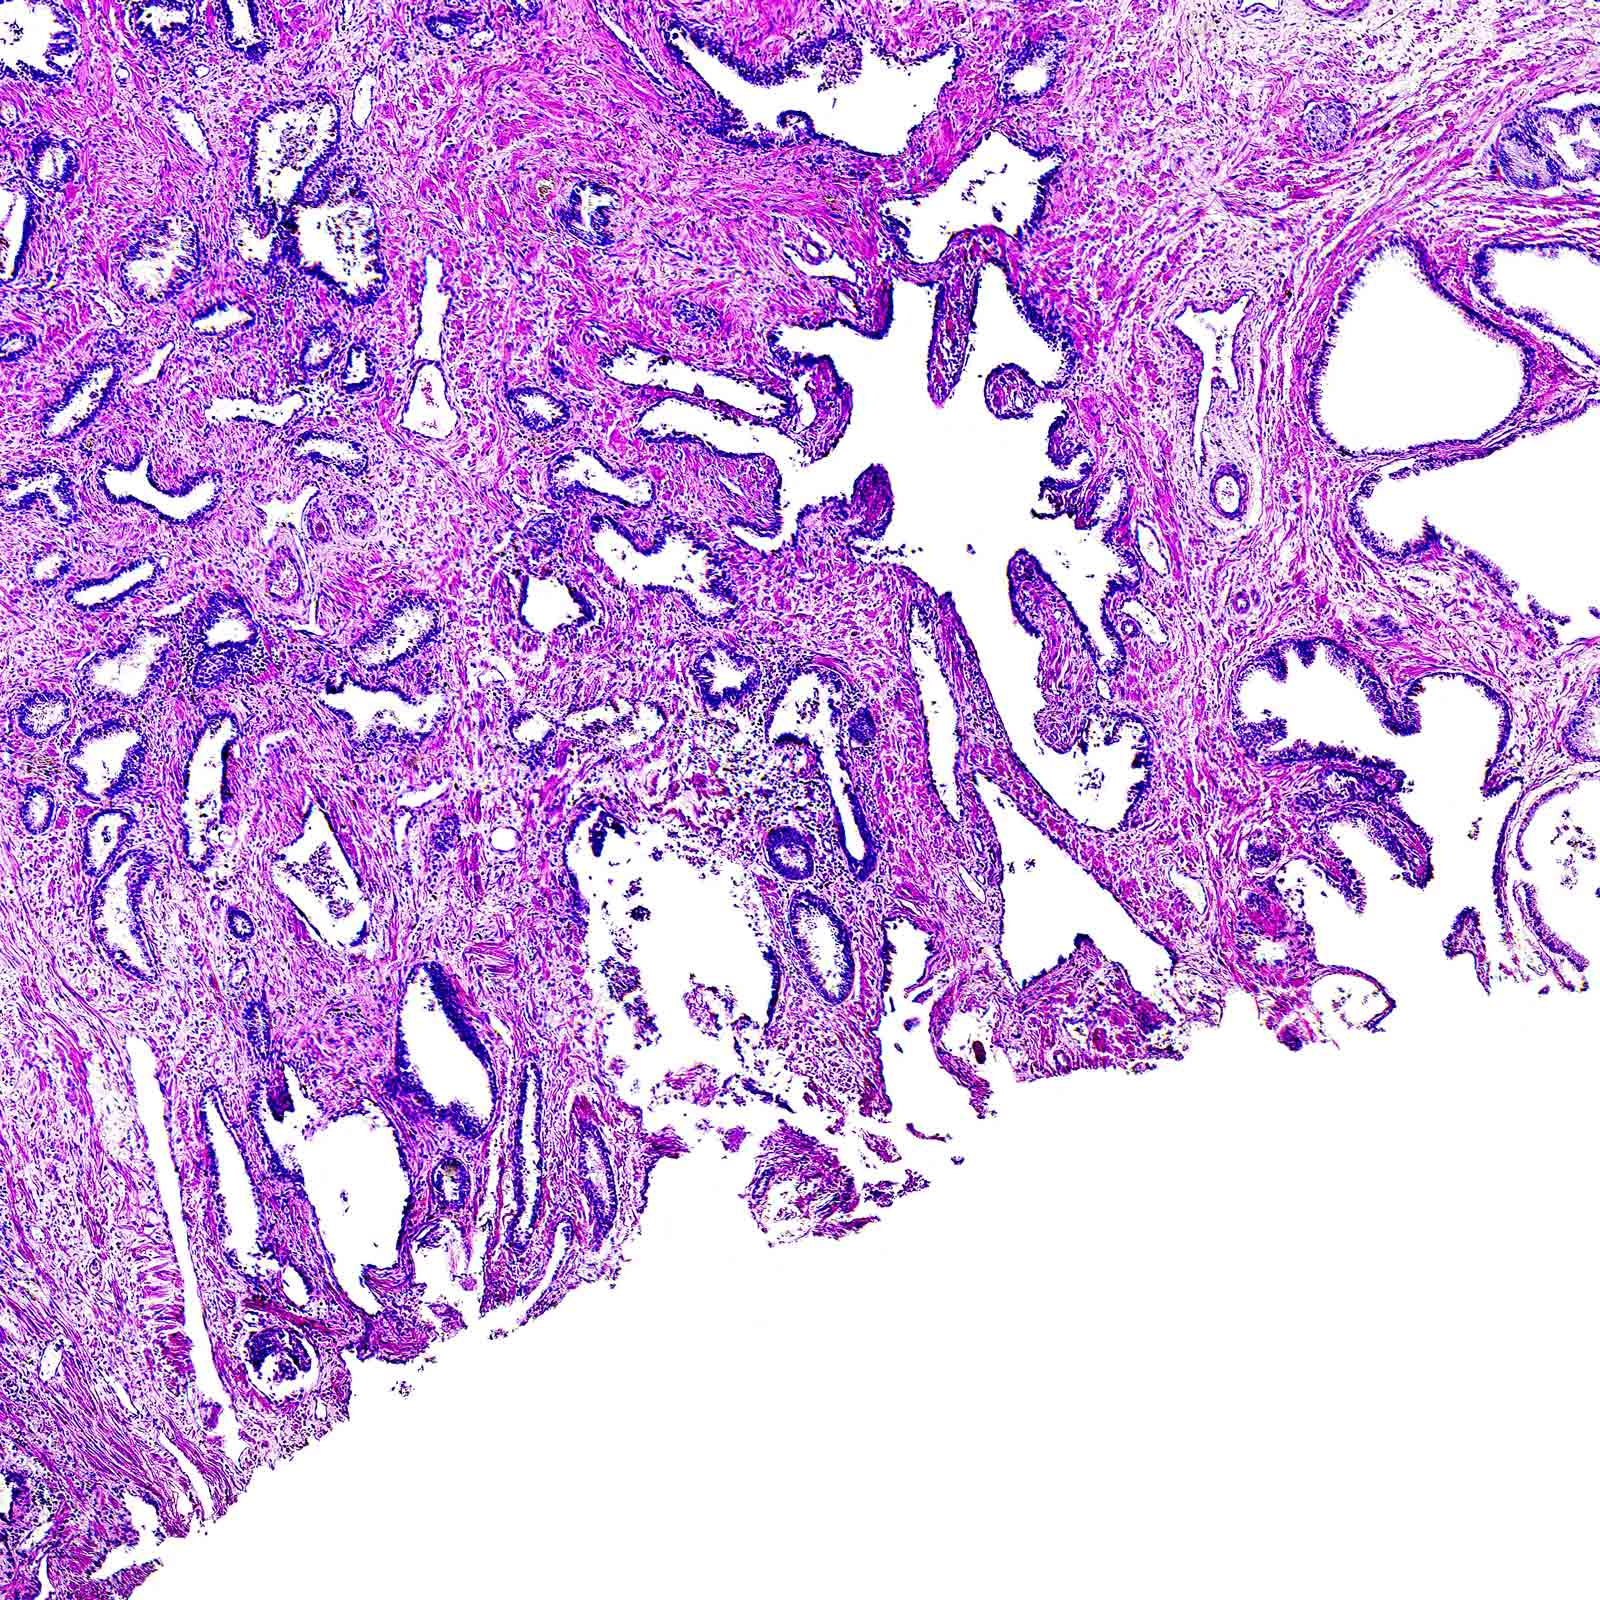

Prostate Smooth Muscle Cells and Fibroblasts

Histopathology of the human prostate cancer progression. ( a …